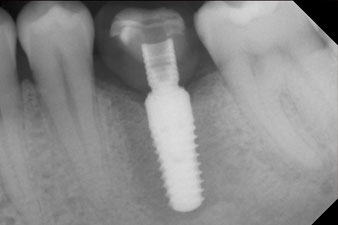

The implant was placed as planned after thorough removal of the granulation tissue (blueSky, bredent).

The torque used for the machine-driven placement was 43 Ncm. In addition, after screwing a measuring post (SmartPeg) specially matched to the implant, the ISQ value was measured with the probe of the W&H Osstell ISQ module.

This module is an optional extra for the W&H Implantmed and is docked to the implantology motor (see Fig. 11). The dimensionless ISQ value immediately after insertion was 64 orovestibular and 68 mesiodistal (maximum value = 100).